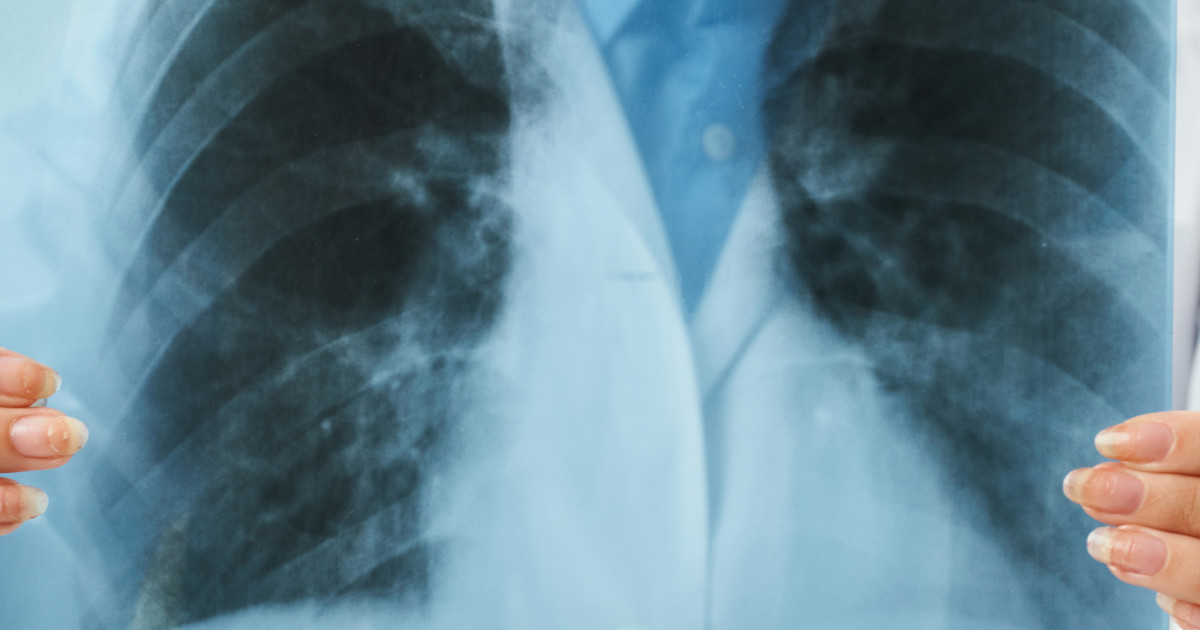

Chest X-Ray

A chest x-ray is a powerful diagnostic tool, including when doctors suspect that their patient has aspiration pneumonia. Doctors will order one for symptoms such as chest pain, coughing, and shortness of breath. A chest x-ray will provide doctors with a detailed view of the patient's lungs. It can reveal fluid that is in or around the lungs, along with air abnormalities. Thus, it can show a build-up of sputum and other lung issues that are often present with aspiration pneumonia. Chest x-rays are quick and effective tests. Patients will receive results within twenty-four hours, often in only a few hours, which is vital in diagnosing aspiration pneumonia.